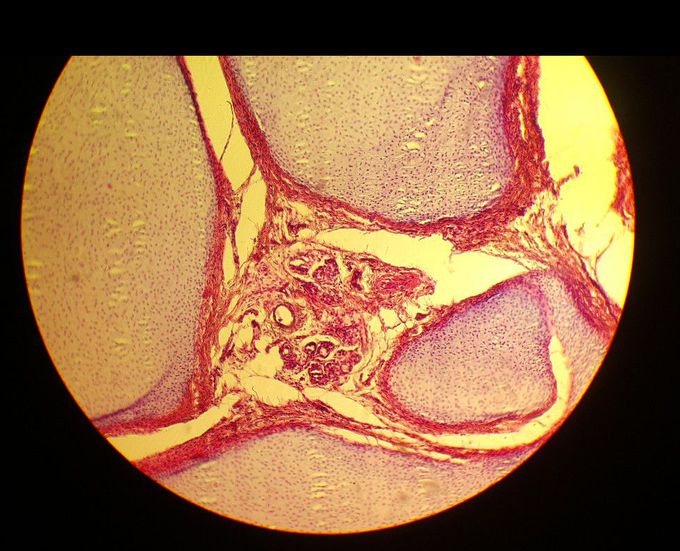

What's your dx??

1. Teratoma 2. Invasive ductal carcinoma 3. Osteosarcoma 4. Chondroma